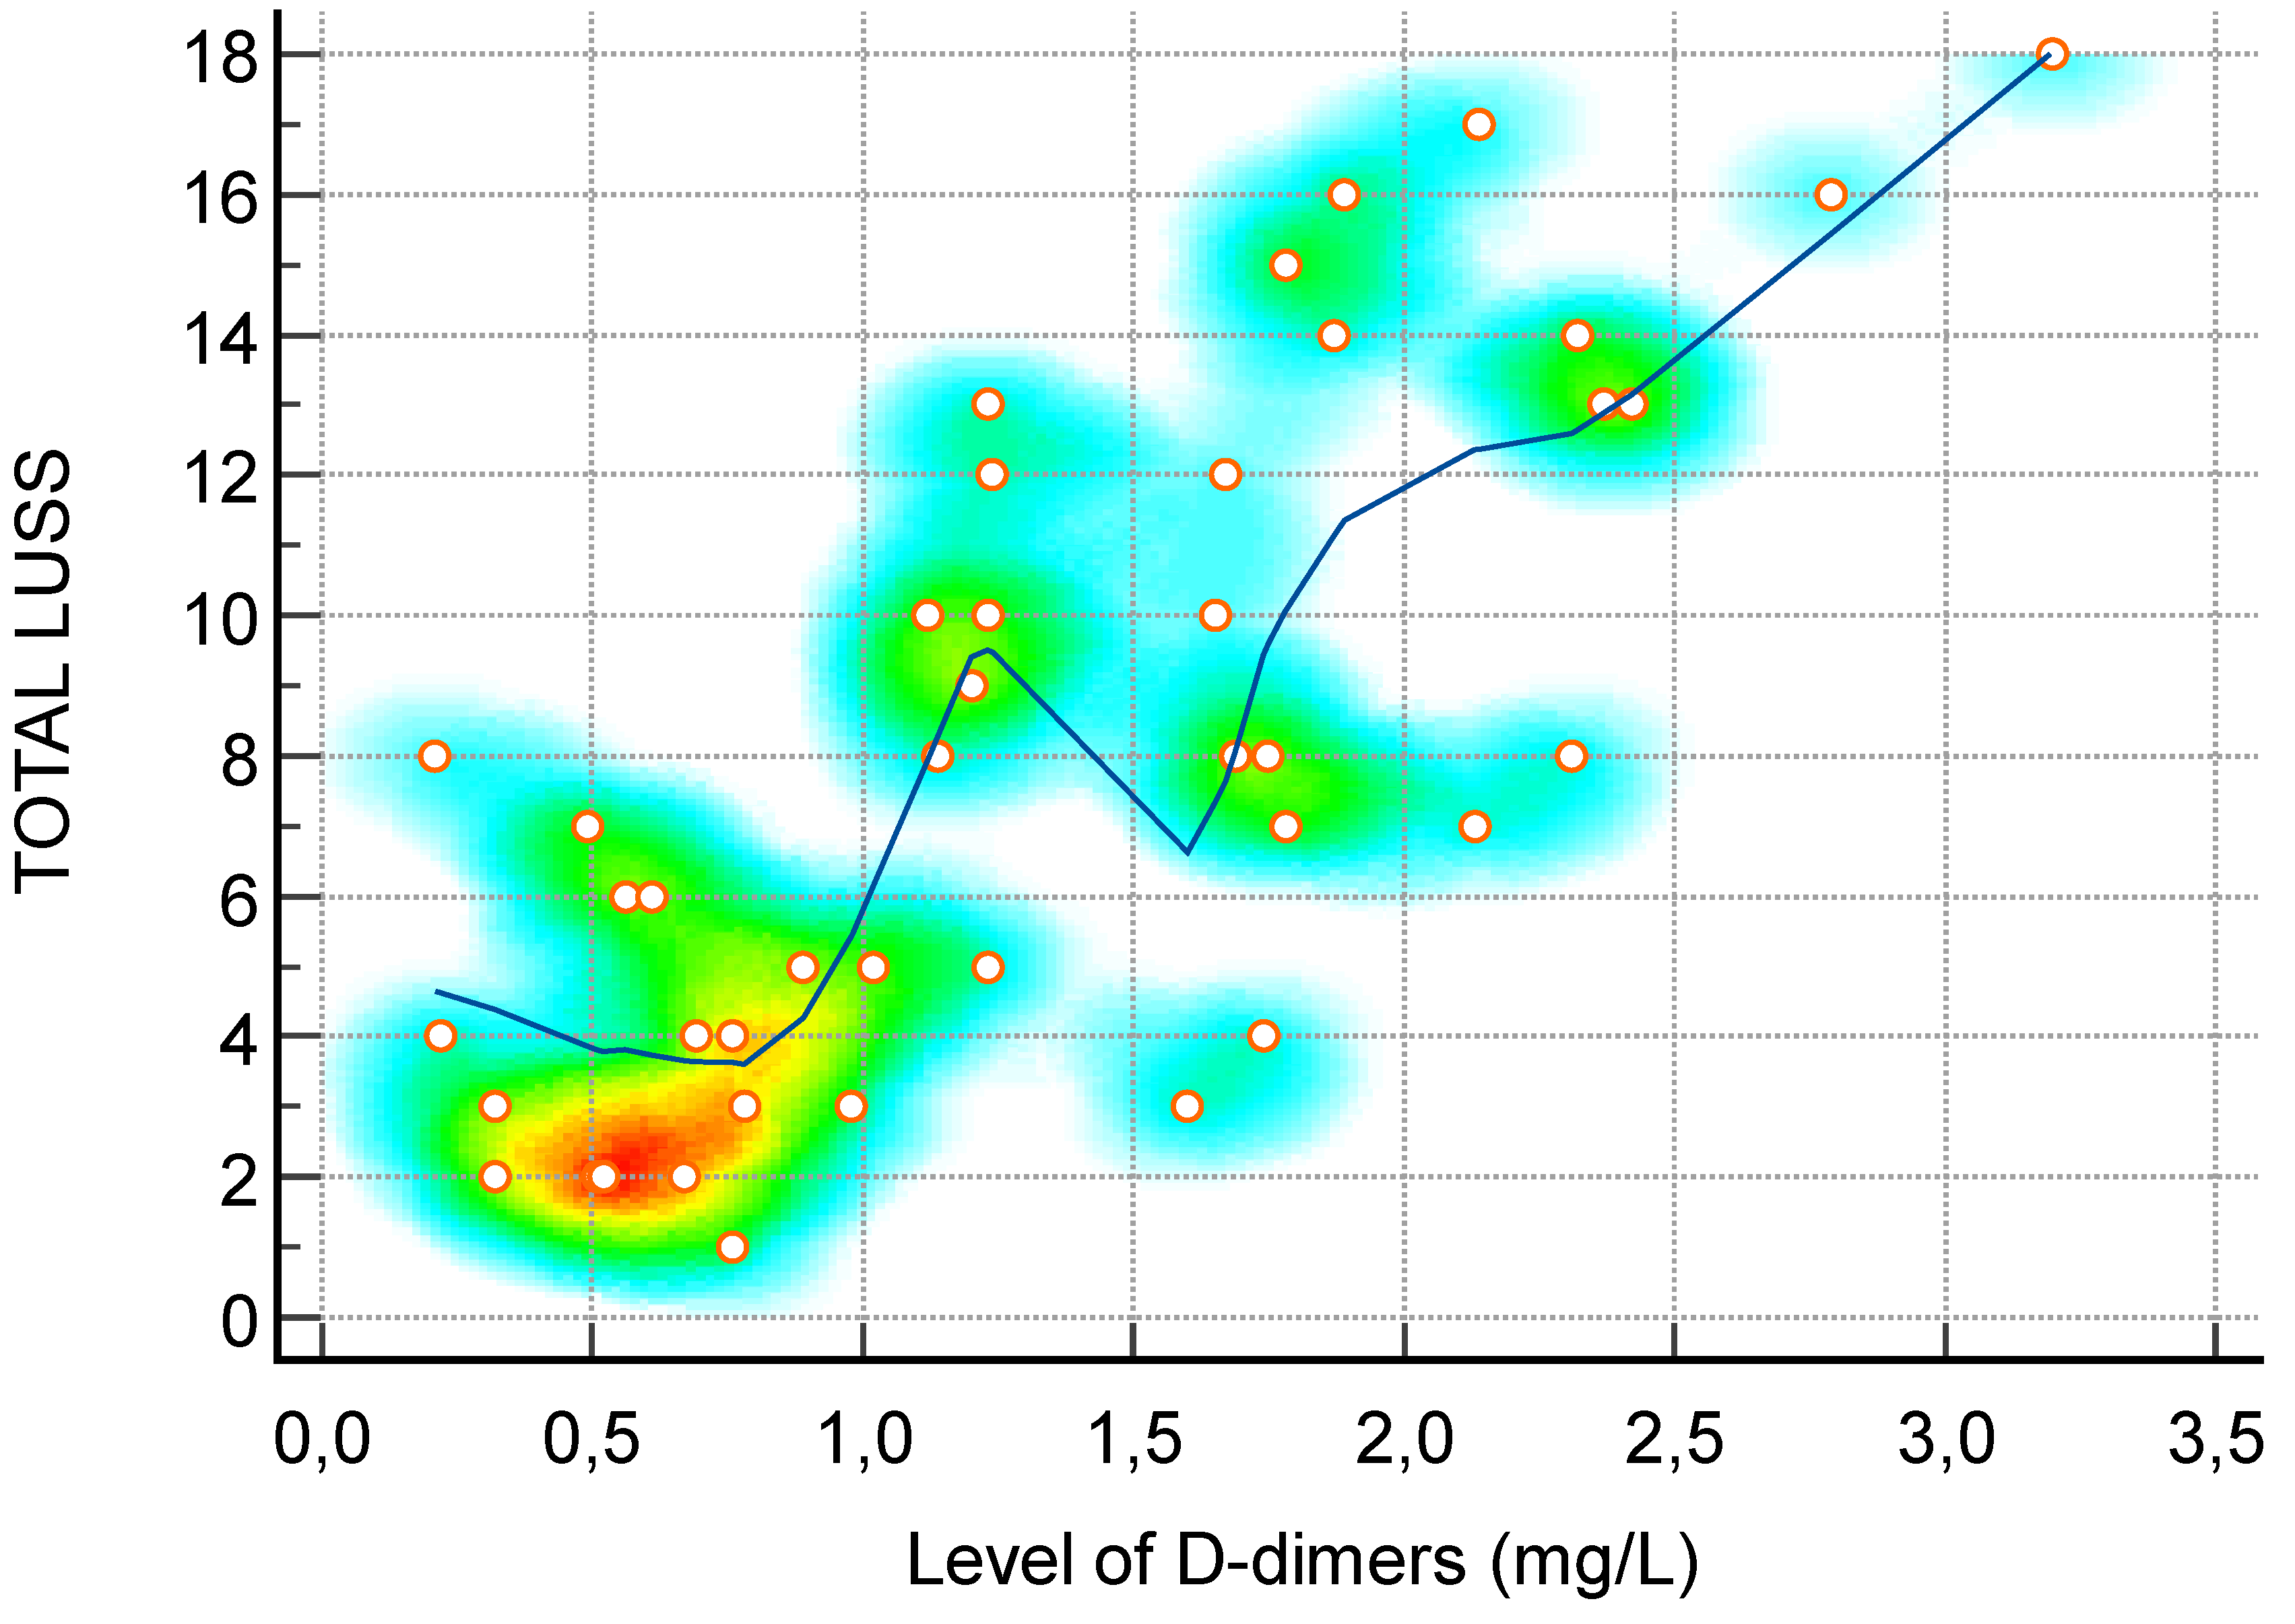

| D-dimer (mg/L)—Figure 5 | 0.73 | 0.55 to 0.85 | <0.0001 |

3.4. Lung Ultrasound Score and Correlation with Inflammatory Markers